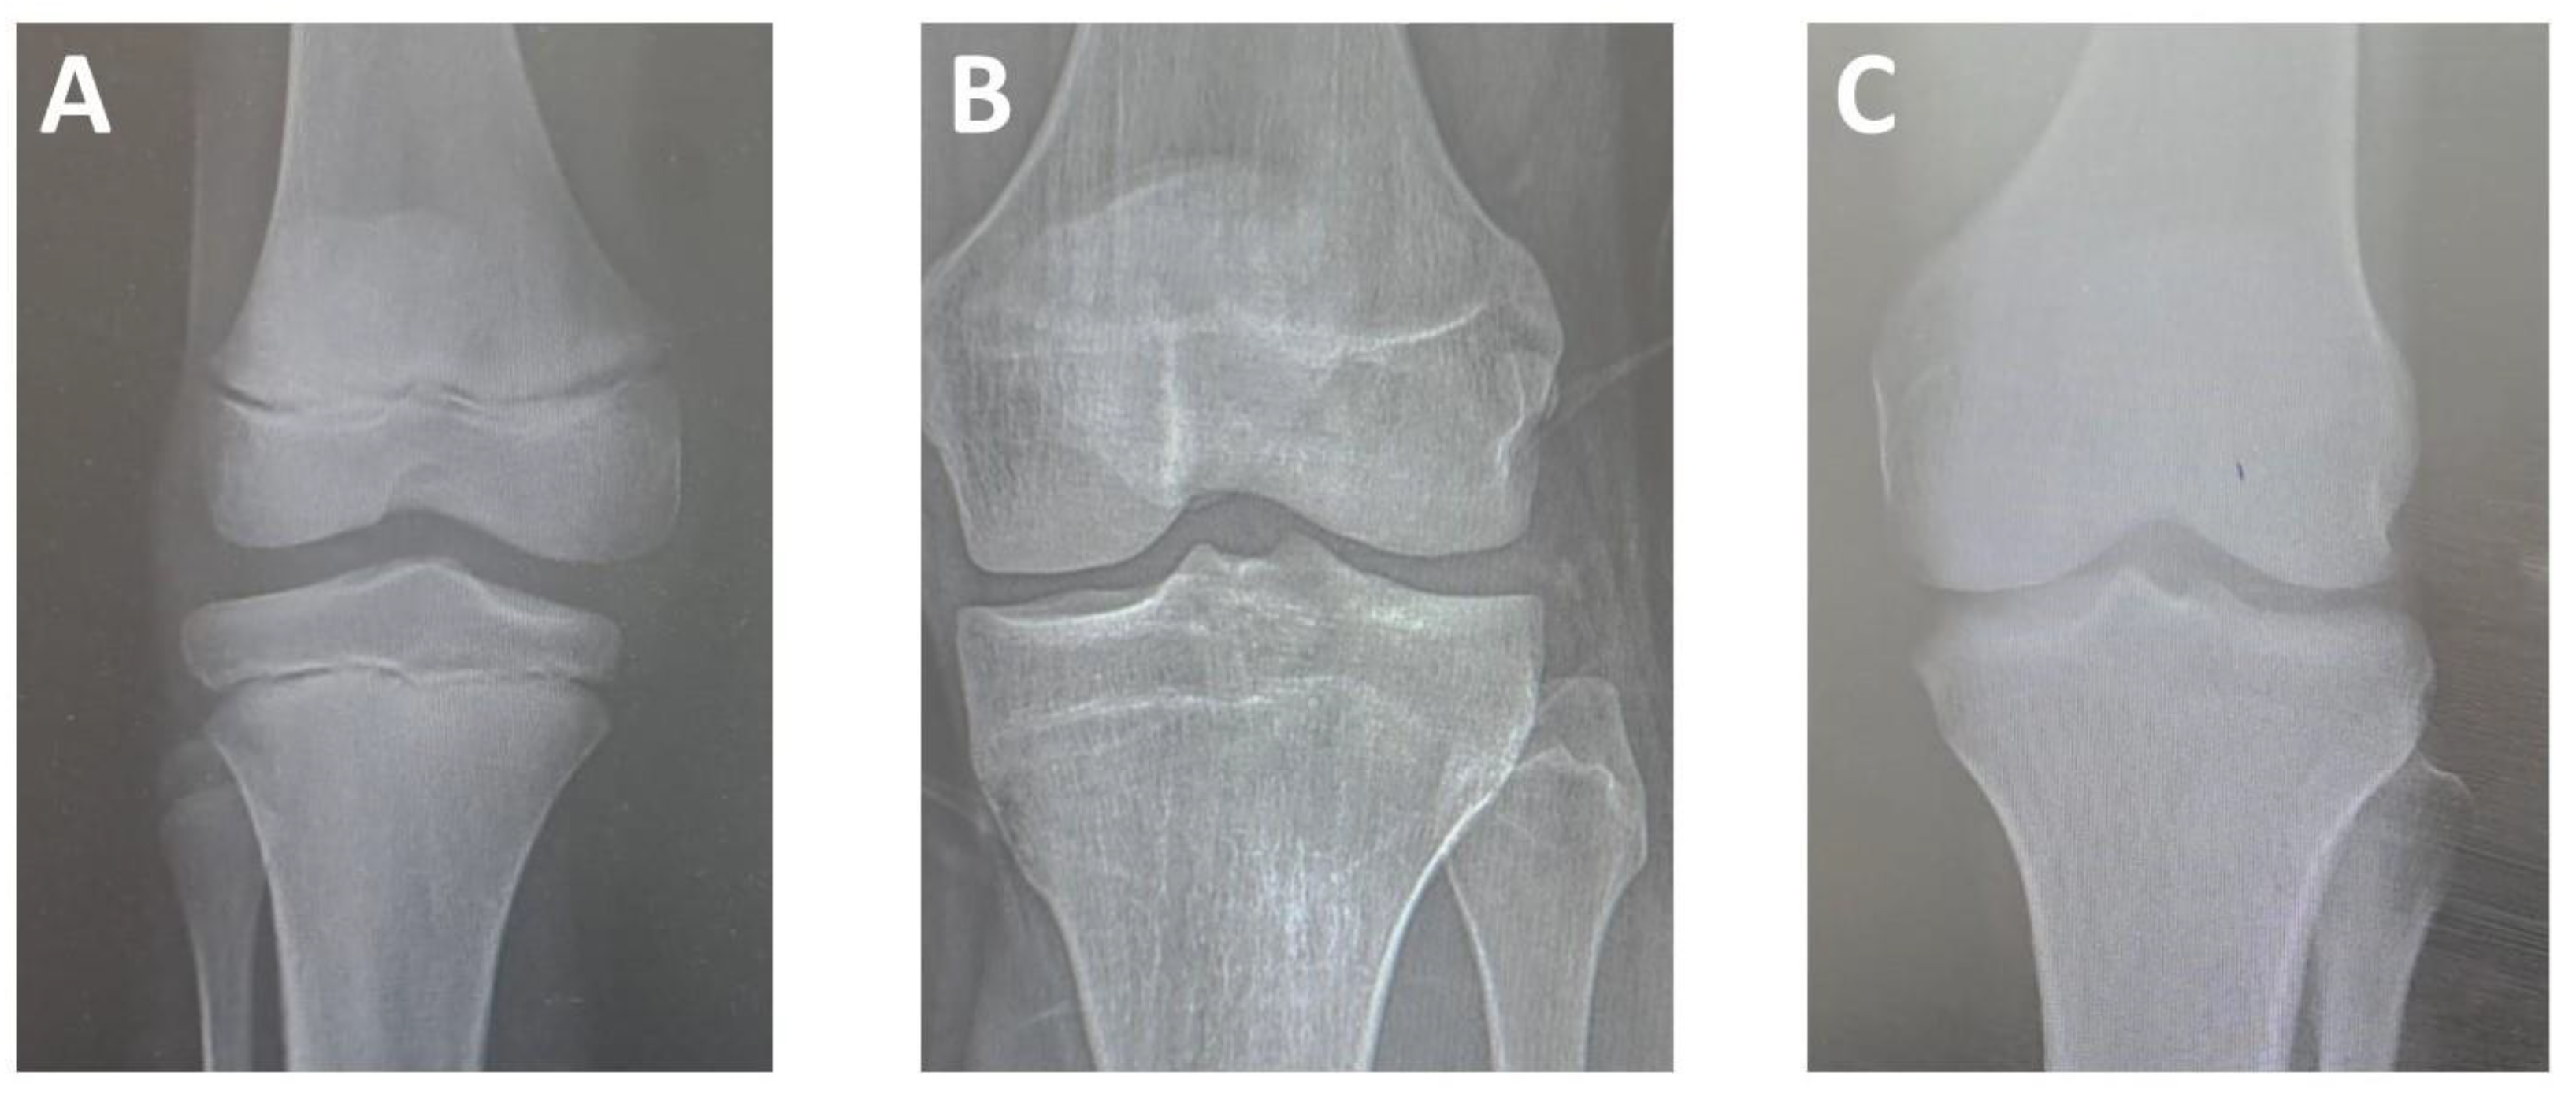

Bone Age Determination of Epiphyseal Fusion at Knee Joint and Its Correlation with Chronological Age

3.1. Lower End of Femur

3.2. Upper End of Tibia and Fibula